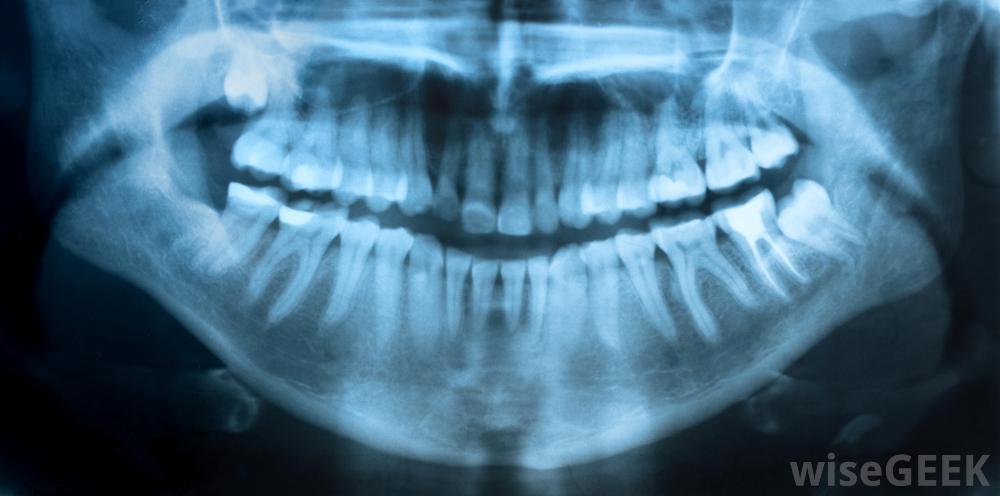

矫正助理可以帮助管理牙科x光片。正畸学是牙科学的一个专门领域,专门研究牙齿和颌骨的排列问题。正畸患者通常是需要长期牙齿的儿童注意矫正牙齿。矫正助手通常在牙齿校准过程中与正畸医师一起工作。他们履行诸如制作牙齿印模、调整牙套和拍摄X光片等职责。矫正助理还可以清洁和安装设备,为患者准备牙科手术,或获取牙科记录。